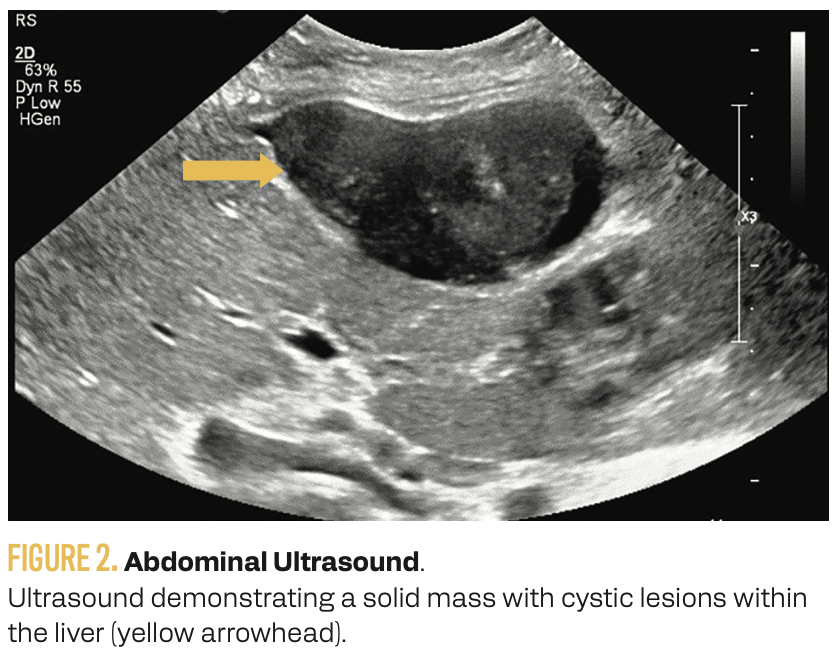

On physical examination, a palpable mass was noted in the midabdomen, extending to the right upper quadrant. Complete blood count and comprehensive metabolic panel were unremarkable. An abdominal ultrasound revealed a solid mass with cystic lesions within the liver (Figure 2). An abdominal CT scan demonstrated extensive perihepatic and intrahepatic lesions suggestive of metastasis (Figure 3). A colonoscopy showed only diverticular disease, and a bilateral screening mammogram result was normal.

FIGURE 2. Abdominal Ultrasound.